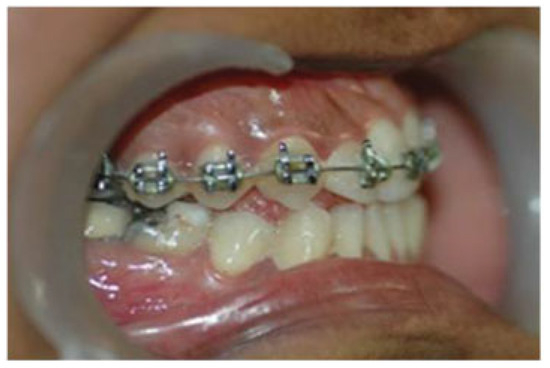

A Modified Kole's Osteotomy for Correction of Anterior Open Bite and Macrogenia in a Cleft Patient

:Surgical Method